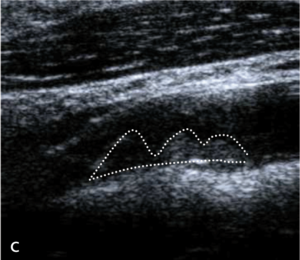

Badaniem ultrasonograficznym można uwidocznić zwężenie i ocenić jego morfologię.

Morfologia zmiany miażdżycowej nie stanowi według standardów kryterium kwalifikacyjnego do rewaskularyzacji, ale wykazuje silny związek z ryzykiem udaru niedokrwiennego mózgu zarówno u chorych leczonych zachowawczo, jak i okołozabiegowego IS w czasie rewaskularyzacji [18].

Zmiany hipoechogeniczne to zmiany częściej lipidowe lub skrzepliny, zmiany izoechogeniczne to zmiany włókniste, a zmiany hiperechogeniczne zawierają zwapnienia.

Zmiany hipoechogeniczne (skrzeplina, lipidowa) są związane z dużym ryzykiem IS zarówno u chorych dotychczas bezobjawowych, jak i w trakcie CAS czy endarterektomii (carotid endarterectomy, CEA), bo łatwo je uruchomić i rozkruszyć, powodując zatory do tętnic mózgowych [18].